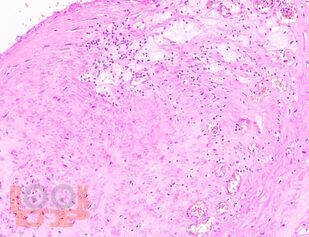

В учебном пособии представлен теоретический материал, перечень макропрепаратов и микропрепаратов, демонстрирующих типовые проявления патологических процессов. В цветных иллюстрациях и в описании микропрепаратов сделан акцент на наиболее важных гистологических изменениях, позволяющих на светооптическом уровне диагностировать и дифференцировать состояния, отклоняющиеся от нормы, в том числе с использованием различных гистологических окрасок. Пособие помогает выделить главные аспекты изучаемых патологических процессов, организовать и конкретизировать учебный процесс.